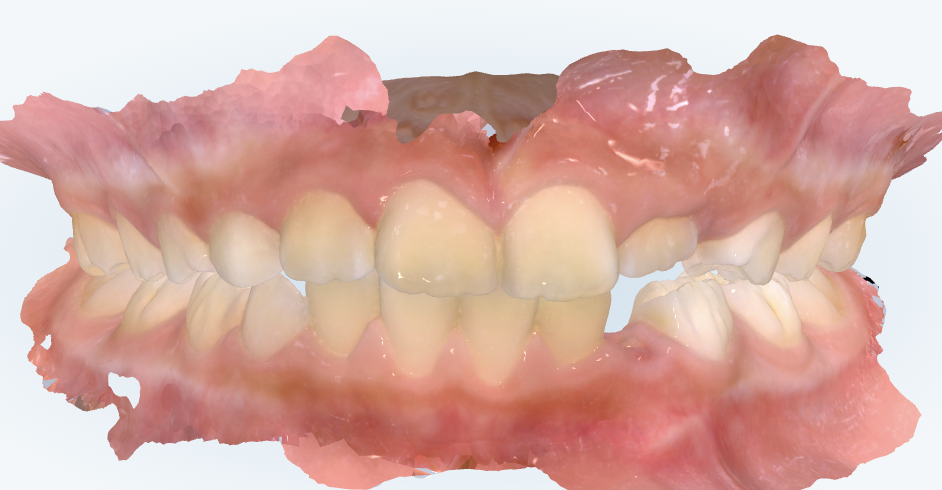

初診時の画像診断

左上の前から3番目の歯(犬歯)が生えるスペースがありません。

奥歯が出っ歯の噛み合わせをしています。

上の前歯の真ん中のラインが左にずれています。